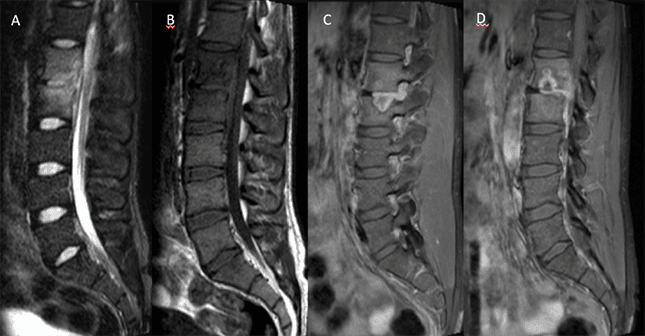

Paciente do sexo masculino, 28 anos, com dor lombar crônica agudizada após trauma direto.

Figura 1.